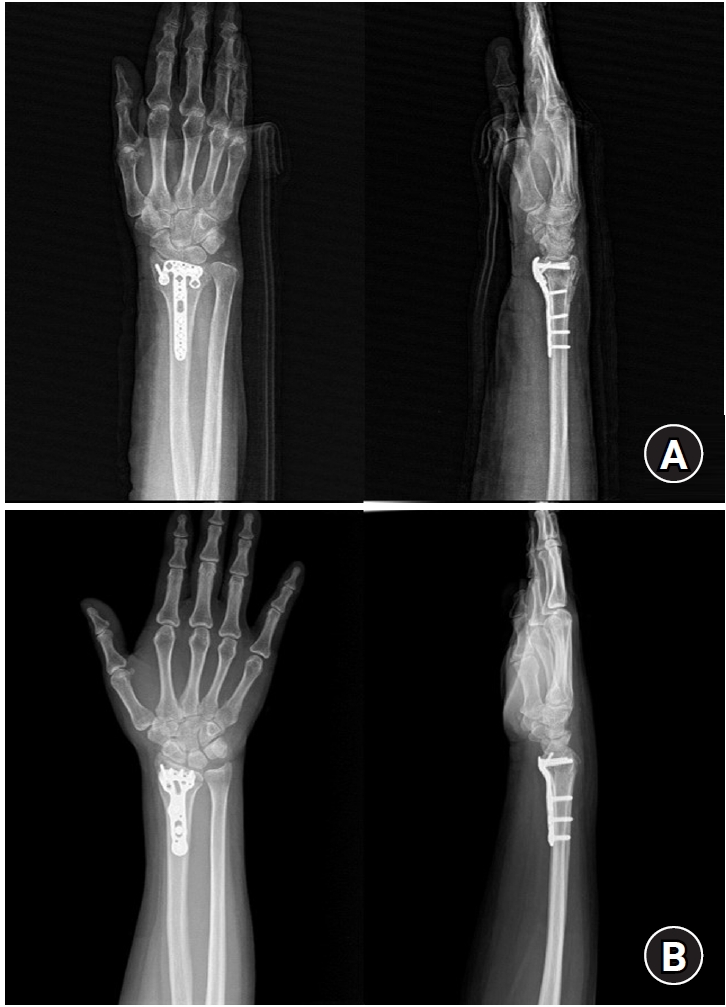

Fig. 4.

Postoperative radiographs (anteroposterior and lateral). (A) A 2.4 mm variable angle locking compression plate volar rim distal radius plate (Synthes) used for fixation in a distal radius fracture with a volar lunate facet fragment. (B) Acu-Loc volar distal radius plate (Acumed) used for fixation in a distal radius fracture with a volar lunate facet fragment.

jmt-2025-00241f4.jpg